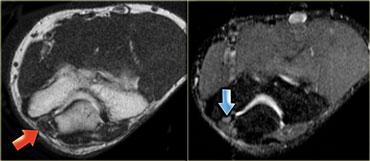

Chuỗi xung T1W có ức chế mỡ sau tiêm thuốc tương phản từ – Các ổ tụ dịch bên trong cơ ngấm thuốc ở bệnh nhân viêm mủ cơ

Viêm cơ do nhiễm trùng

Nhiễm trùng cơ hoặc viêm cơ không có áp xe hay hoại tử có thể chỉ biểu hiện phù nề là bất thường duy nhất trên hình ảnh MRI.

Hình ảnh MRI và tiền sử lâm sàng có thể gợi ý sự hiện diện của nhiễm trùng như vậy.

Viêm cơ do vi khuẩn thường tiến triển thành hình thành áp xe và do đó thường có hình ảnh giống khối trên MRI.

Nhiễm trùng do virus không tiến triển thành hình thành áp xe.

Dấu hiệu đặc trưng của nhiễm trùng cơ là các ổ tụ dịch bên trong cơ (hình minh họa).